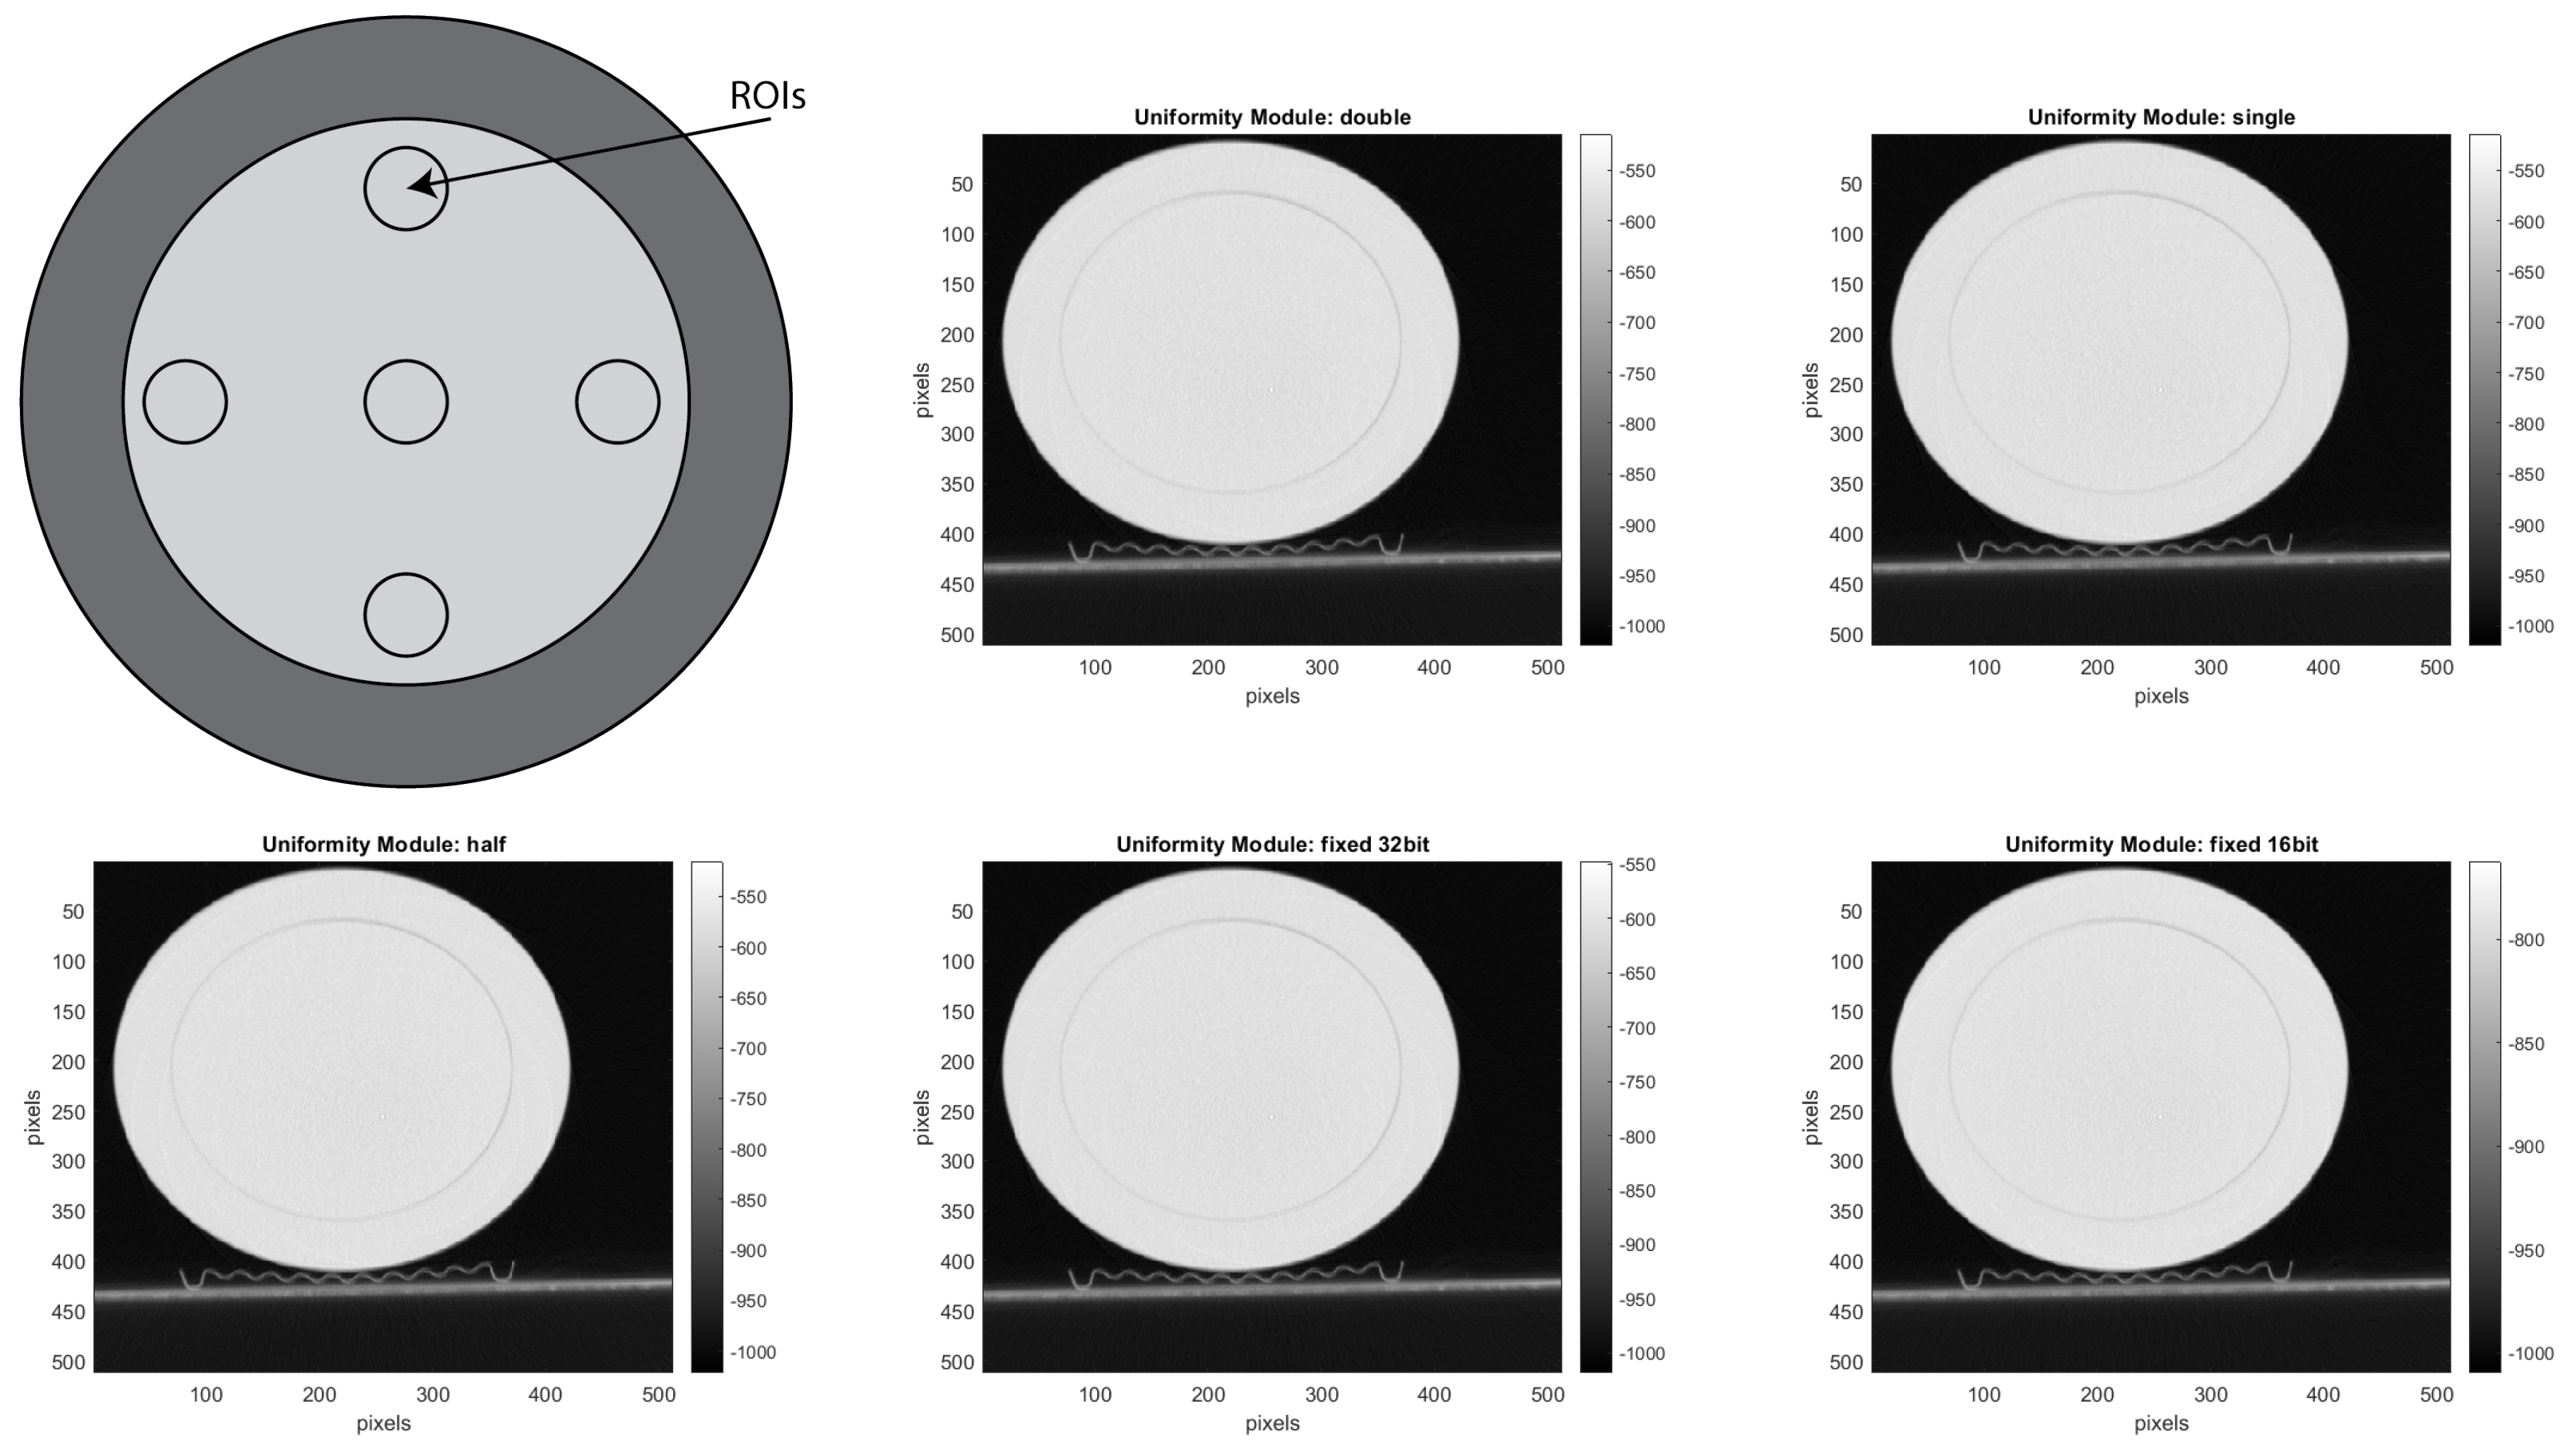

• CTP486 Uniformity Module: This module is cast from a uniform material with a “CT number” designed to be within 2% of water’s density under standard scanning protocols [15]. This module is used for measurements of spatial uniformity, which means CT number and noise value. As shown in Figure 11, this module has a different region of interest (ROI) that can be targeted for measuring the uniformity of the different areas of a phantom section. In fact, the mean CT number and standard deviation of a large number of points, in a given ROI of the scan, is determined for central and peripheral locations within the scan image for each format of the scanning protocol [50].

For calculating the values of the noise, uniformity and low contrast from the reconstructed volume, we considered a different ROI per module, as suggested by the CATPHAN® 500 Manual [15]. For selecting the ROI, we used the reconstructed images shown with red and blue circles in Figure 14, where the pre-processing was done with the double format. For the noise analysis, we calculated the standard deviation of the CT number for each of the ROIs, placed on the uniformity module and shown in Figure 14.

For the uniformity analysis, five ROIs with 40 pixels in diameter are placed on the module, four peripheral ROIs and one central ROI. The average CT number, in HU, is obtained for each of these ROIs, and the uniformity is measured as the maximum difference between the mean value of the center ROI and one of the peripheral ROIs.

Since with the human visual analysis, it is not possible to compare the accuracy and the information lost between the different data formats, we estimated the MSE of the projections. The MSE, as explained in Section 7, is the key point used for reducing the eligible data formats for the DSE. It was crucial to select the two data format configurations of the 16-bit and 32-bit fixed-point; we reduced from 48 to 2 possible data format configurations. The MSE is a reasonable metric in this step because it can be applied to 2D projections before the reconstruction. In addition, we noticed that it is in the same order of magnitude for the different phantoms. However, the MSE does not consider all image quality metrics, which are significant to understanding how data formats influence the quality of reconstructed images. Therefore, we performed the measurement of low contrast, noise and uniformity for the reconstructed images. For calculating these metrics, we acquired, pre-processed with different data format configurations, and reconstructed the modules shown in Figure 17 and Figure 18.

Figure 17. Reconstructed image of the CTP486 module, for noise and uniformity analysis.